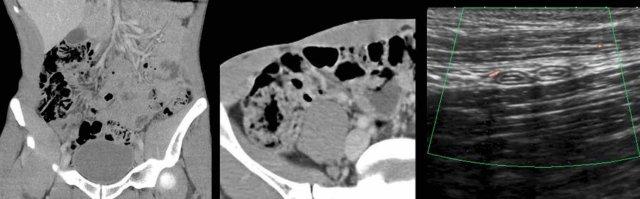

Ở người phụ nữ cao tuổi này với đau bụng không điển hình và suy thận, CT không tiêm thuốc cản quang cho thấy hình ảnh ruột thừa nghi ngờ viêm.

Siêu âm tập trung với đầu dò tần số cao xác nhận ruột thừa nằm ở phía trước bụng đang trong tình trạng viêm.

Ở người đàn ông trẻ này, ruột thừa không thể xác định được trên CT do thiếu mỡ trong ổ bụng.

Siêu âm dễ dàng xác định được ruột thừa bình thường.